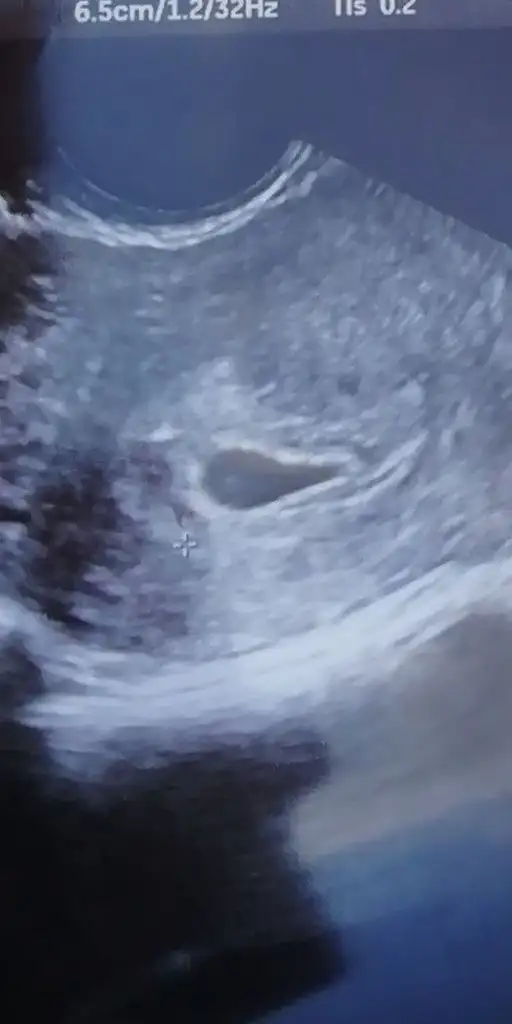

kızlar merhaba yorumlarınızı takip ediyordum ama yazamıyordum sata göre gebeliğim 7+6 hastaneye gitmiştim ama doktor bebeği görememişti boş gebelikten şüphelendi bugün sat 8+3 şükürler olsun meleğimi gördüm ve kalp atışını duydum meğerse bende geç döllenme olmuş ve gebelik 7+1 haftasındaymış eğer aranızda daha meleğini göremeyenler varsa sakın korkmasınlar bol bol su içsinler ve dinlensinler beslenmeyede dikkat etsinler çünkü bu durumu yaşadım ben allah kimseye yaşatmasin inşallah sağ salim evlatlarımızı kucagimiza alırız